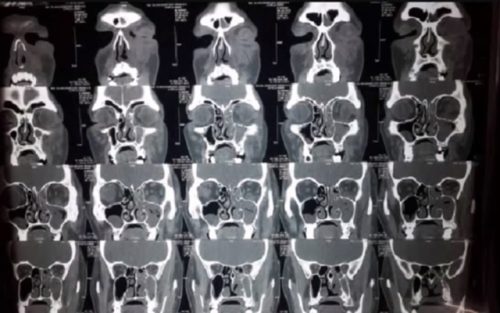

এই চিকিৎসক জানান যে রক্ত, চামড়া, মুখ, নখসহ শরীরের নানা জায়গায় ব্ল্যাক ফাঙ্গাস ইনফেকশন হতে পারে এবং সাধারণত রক্ত পরীক্ষার মাধ্যমে এটি চিহ্নিত করা সম্ভব হয়।

১। নাক বন্ধ হয়ে আসা, ন্নাক থেকে চাপা রক্তের মতো বা কালো পুঁজ বেরনো।

২। চোয়ালে বা উহের এক দিকে ব্যথা, অবশ হয়ে যাওয়া বা ফুলে যাওয়া।

৩। নাকের উপর কালছে দাগ

৪। দাঁতে ব্যথা বা দাঁত আলগা হয়ে আসা

৫। দৃষ্টি ঝাপসা হয়ে আসা বা দুটো করে জিনিস দেখা, জ্বর, ত্বকের সমস্যা।

৬। বুকে ব্যথা, নিঃশ্বাসের সমস্যা বেড়ে যাওয়া।